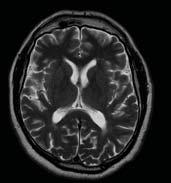

CHICAGO – In a demonstration at the RSNA conference last December, Dr. Luciano Prevedello, a radiologist at Ohio State University’s Wexner Center of Medicine, chatted with his AI-enabled computer about a patient’s brain lesion as he created a report. He showed how he could discuss the case with an AI agent, much like he would with a colleague.

Not only did the AI agent offer expert opinions on the lesion’s type and location, but it could also bring up different patient exams on the computer screen, including CTs and MRIs that had been taken, with a variety of views.

But the most astounding changes are appearing on the reading and reporting side. Dr. Prevedello demonstrated work under development at Ohio State University’s medical center, where AI agents are analyzing entire imaging studies and providing full reports with diagnoses.

In an impressive demonstration, Dr. Prevedello discussed a patient’s images, in natural language English, with an AI agent.

The agent stated in a clear voice, “Okay, I see a screen with a presentation. It mentions progressive visual disturbance with bitemporal hemianopsia. And it shows it’s a 35-year-old female.”

The agent then asks, “Is there anything else you would like to discuss?”

Dr. Prevedello said, “What do you think about this history? The patient’s history is concerning.”

The agent responded, “Progressive visual disturbance with bitemporal hemianopsia suggests a lesion at the optic chiasma. Is there anything else you would like to discuss?”

“Yes, I would like to see the images. What do you see?”

“Yes, I would like to see the image of the bone window, okay?”

The agent and the doctor go on to look at

The AI agent brings up images and says, “I see a CT scan of the brain. It’s an axial view and I see a possible mass in the region of the sella. Would you like to see anything else.”